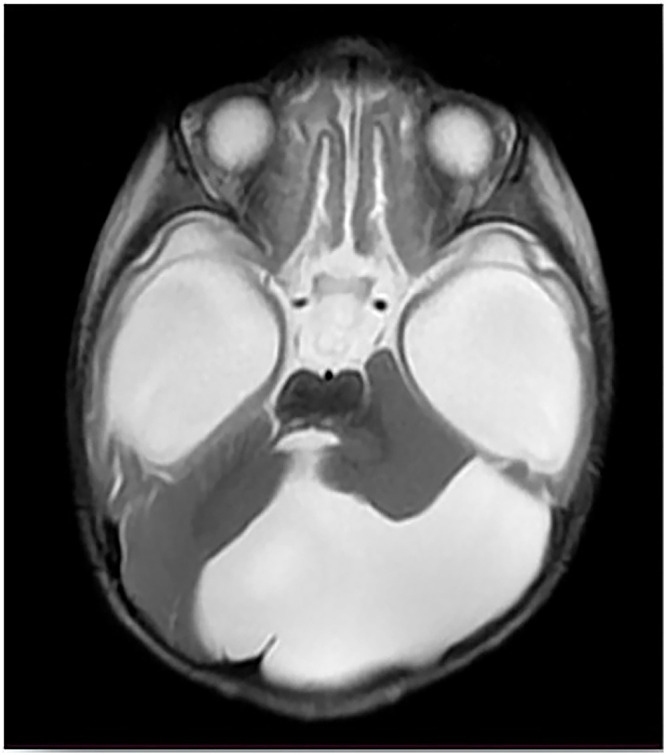

Dandy-Walker Syndrome (DWS) is a rare cerebellar malformation characterized by the underdevelopment of the cerebellar vermis and associated complications. This case report presents a 3-month-old female from Somalia who exhibited fever, loss of consciousness, vomiting, and developmental delays. Neurological examination suggested signs of meningitis, and MRI revealed an enlarged posterior fossa consistent with DWS. Despite initial antibiotic treatment for suspected bacterial meningitis, CSF cultures yielded no growth, raising concerns about prior antibiotic use. Unfortunately, the patient's condition deteriorated, leading to her death. This case highlights the diagnostic challenges of DWS in resource-limited settings and emphasizes the need for improved healthcare access, early diagnosis, and intervention for rare neurological conditions.